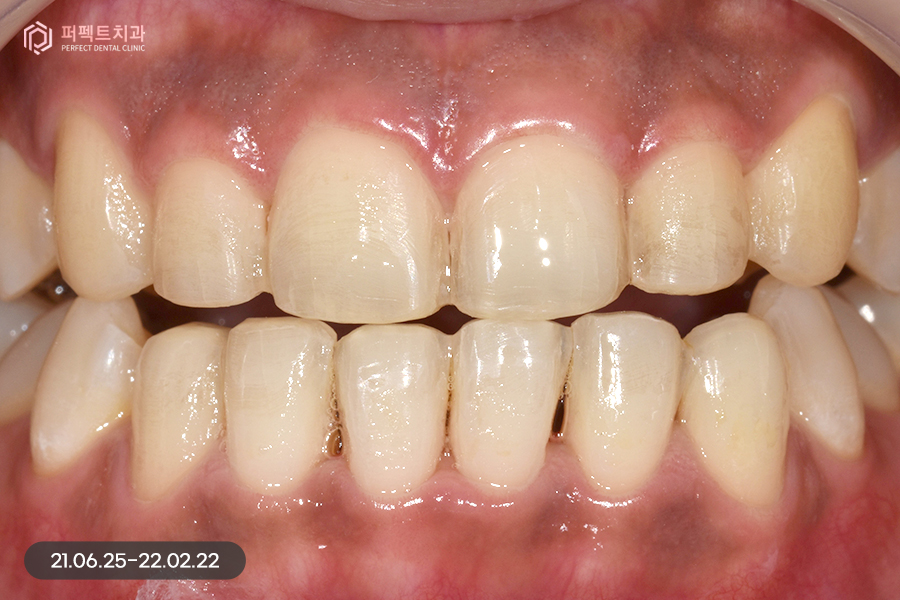

사진으로 보았을 때 큰 문제가 없어보이지만 실제로는 위 아래 치열이 삐뚤빼뚤하고 아래 치아의 경우 위 치아보다 더 틀어짐이 심했는데요. 그렇기 때문에 부분교정을 5개월 정도 진행하였습니다.

교정 후 치아가 가지런하게 펴졌는데, 교정을 하면 항상 생기는 문제점 중 하나가 바로 고르지 못한 치아들이 가지런하게 펴지면서 잇몸 사이 공간인 블랙트라이앵글입니다.

위 환자분도 마찬가지로 블랙트라이앵글이 발생했고, 이 공간을 해결함과 동시에 치아 색상도 하얗게 변화를 주길 원하셨습니다. 그렇기 때문에 위, 아래 6개 치아를 라미네이트 진행하였습니다.